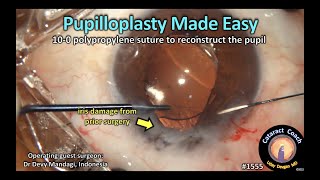

Advanced Anterior Segment Clip #1 Pupillary cerclage CataractCoach 1555: pupilloplasty made easy (iris reconstruction)

CataractCoach 1555: pupilloplasty made easy (iris reconstruction) KERAKONNECT - Masterclass on The ART of PUPILLOPLASTY and IRIS REPAIR in Challenging Situations

Advanced Anterior Segment Clip #1 Pupillary cerclage CataractCoach 1555: pupilloplasty made easy (iris reconstruction)

CataractCoach 1555: pupilloplasty made easy (iris reconstruction) KERAKONNECT - Masterclass on The ART of PUPILLOPLASTY and IRIS REPAIR in Challenging Situations